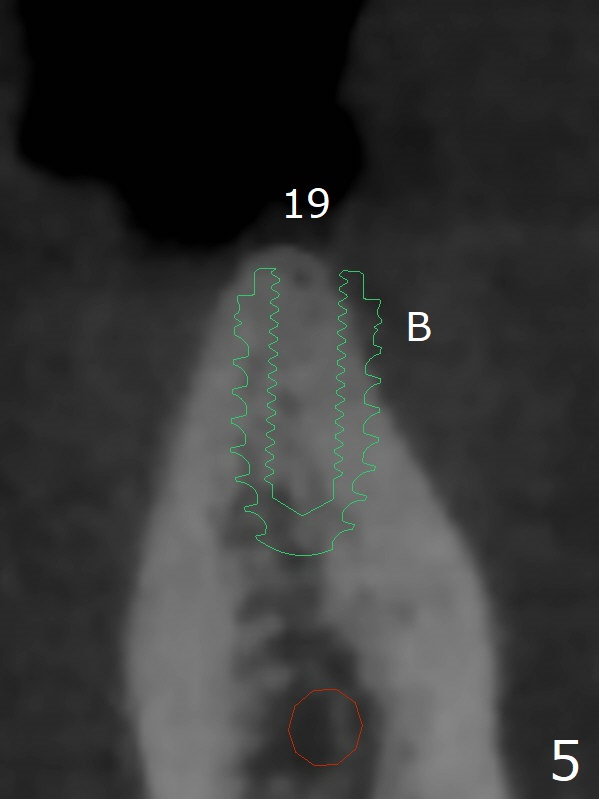

When implants at #4, 13 and 14 are placed, the patient wonders how many more implants are needed. From 0 (considering a lower RPD) to 5 (#3, 19, 20, 25 and 30). The tooth #3 seems to have periodontal-endodontic disease (Fig.1,2). Since the ridge is narrow at #19 and 20 (Fig.3), ridge split at #19 and a 1-piece implant at #20 are planned (Fig.4,5-9). The implant at #19 will be placed in an ideal prosthetic position (Fig.5). The ridge transverse bony cut will be made free hand in the middle (Fig.6,6'), followed by 2 vertical cuts and 1 apical transverse one in the 1st stage of procedure. In order to rotate the buccal block easier (Fig.6 pink curved arrow), the apical transverse cut will be wedge in shape (Fig.6 (red), 6' (double lines), 7 (black)). In the 2nd stage, the ridge top split will be extended by using a chisel (Fig.7 longer red line) and the buccal block will be pushed buccally (Fig.8). A guide will be seated to finish osteotomy (Fig.9 white) and implant placement.